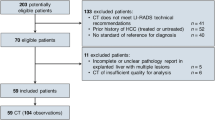

This retrospective study included 502 CRC patients who underwent contrast-enhanced CT and contrast-enhanced liver MRI between January 2005 and December 2010. Portal-phase CT images of training (n = 386) and validation (n = 116) cohorts were used to develop a radiomics model for differentiating three classes of liver lesions. Among multiple handcrafted features, the feature selection was performed using ReliefF method, and random forest classifiers were used to train the selected features. Diagnostic performance of the developed model was compared with that of four radiologists. A subgroup analysis was conducted based on lesion size.